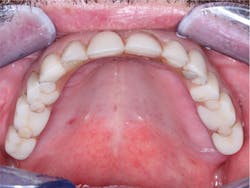

Oral hygiene—When patients with a removable prosthesis have eaten and food debris are left under the denture, they can easily clean the prosthesis in seconds by taking it out and cleaning it in their hands. Many fixed prostheses, such as the ones shown in Figures 1 and 2, cannot be cleaned well. Cleaning requires significant time and effort, and there is often not adequate access to allow cleaning under the prosthesis. The result is usually red, inflamed, and sometimes painful soft tissue (figure 3). If significant ridge lap has been necessary for esthetic reasons, such as that shown in Figure 4, the result may be not only inflamed and irritated soft tissue, but also bad breath caused by the stagnant food debris that are impossible to remove from underneath the prosthesis.

Figure 4: I placed this fixed prosthesis 20 years ago, and it had to have more facial fullness to reduce the typical sunken facial form. After 20 years of service, the irritation of soft tissue is still obvious.